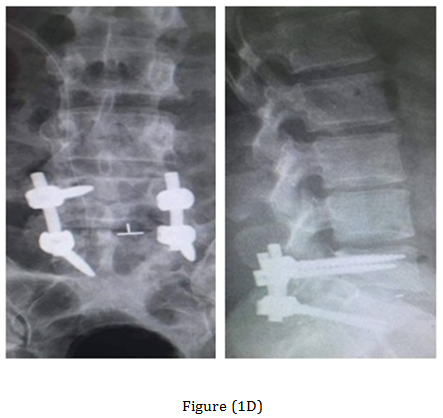

The post-operative Antero-posterior, lateral radiographs and dynamic views were used to assess the fusion mass at each level. The plain radiographs were obtained at 3 months, 6 months, 12 months, 18 months and 24 months to assess fusion status. Solid arthrodesis of the interbody space was confirmed by the presence of continuous bridging bone observed on the lateral radiographs, absence of lucencies around the cages, no cage migration or collapse and absence of halo around the screws. By Using this criteria, solid fusion was achieved in 18 patients (90%), whereas pseudarthrosis was documented in two patients. Low back and leg pain were completely resolved in 18 patients (90%) according to VAS (Table 1). All patients were rated minimal disability according to ODI (Table 2). The radiological outcome (Figure 1) showed solid fusion was achieved in 18 patients (90%), whereas pseudarthrosis was documented in two patients.

Figure 1 Case 3 with L.D.P L5-S1. (A) Preoperative radiograph anteroposterior and lateral views. (B) Preoperative MRI. (C) Post-operative radiographs anteroposterior and lateral views. (D) At the 18-months follow up anteroposterior and lateral views radiograph.